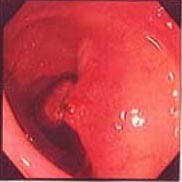

(1)長い茎をもつポリープが発見されました。左上がポリープの頭部で、右下が基部です。 |